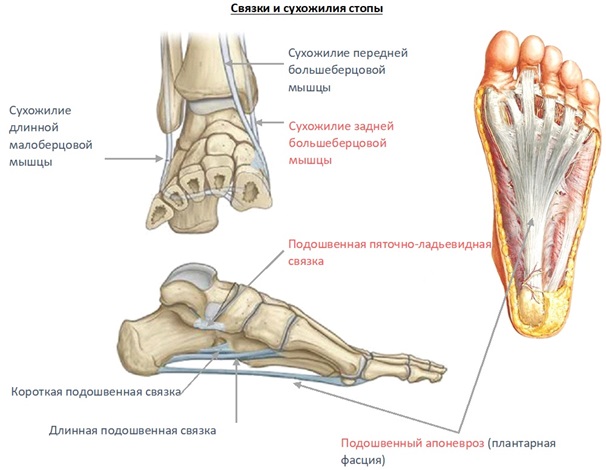

Анатомия голеностопа: Сухожилия и их строение